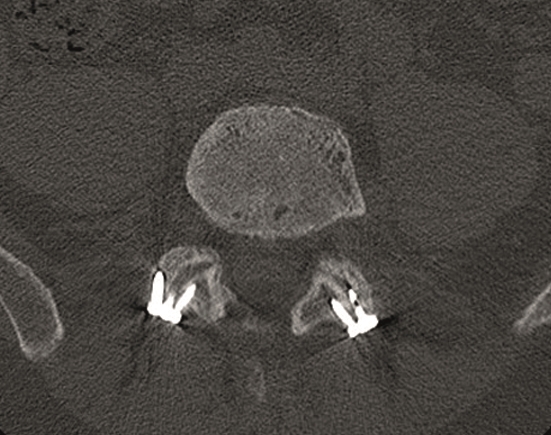

A female patient 66-years-old with back pain, leg pain, and degenerative deformity. The x-rays show left convex degenerative scoliosis Cobb T12-L3 38. Nonoperative treatment failed. Treatment option was posterior fusion T11-L5, with URS Facet Wedge L2-L3 unilaterally.

A conventional approach for posterior correction was taken, with indirect Foraminal decompression and Facet Wedge fusion (apex curve). Facet Wedge introduction after curve correction with rod in situ. X-ray follow-up initially (Fig 20), with CT assessment of Facet Wedge fusion after 6 months (Fig 21).